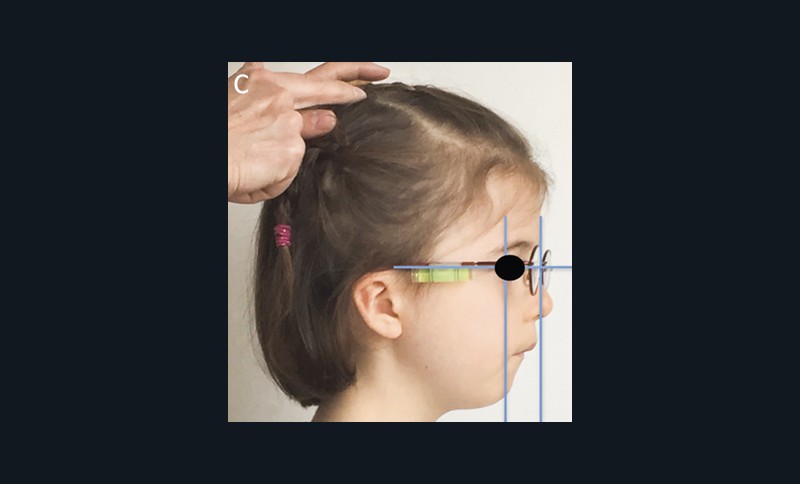

Examen exobuccal

L’examen clinique orthodontique débute par un examen exobuccal de face et de profil qui permet à l’orthodontiste d’identifier certains signes d’appel du Sahos [4]. L’examen de face apprécie la forme globale du visage, la typologie et la symétrie faciale (fig. 5). Des signes caractéristiques sont souvent rapportés chez les enfants suspectés de Sahos : incompétence labiale au repos, hypotonie de la lèvre supérieure avec un angle naso-labial augmenté, visage allongé, orifices narinaires étroits et pincés et présence de cernes (fig. 6a) [5]. Ce sont des indicateurs indirects d’une obstruction ou d’un rétrécissement nasal et d’une ventilation buccale [5-6].

L’examen de profil apprécie les rapports maxillo-mandibulaires et la convexité du visage dans le sens antéropostérieur. Chez les enfants apnéiques, on note généralement la présence d’un profil convexe rétrusif avec un menton en retrait, associé à des dépôts graisseux si l’enfant est en surpoids. Une hypotonie de la lèvre supérieure, qui se traduit par un angle naso-labial ouvert, signe d’un hypo-développement maxillaire, est souvent présente [7]. Enfin, on observe parfois une contraction du muscle mentonnier associée à une occlusion labiale forcée (fig. 6b).